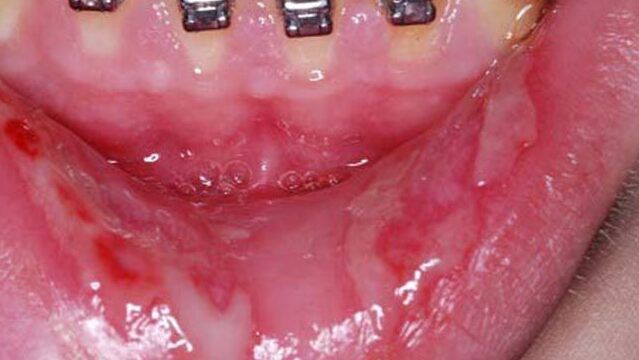

Uno de los síntomas más comunes de la alergia al níquel en la boca es la aparición de una erupción cutánea o bultos en la piel. Estos pueden ser pequeñas protuberancias rojas o ampollas que se forman en la zona afectada. La erupción puede ser dolorosa y causar molestias significativas.

El enrojecimiento de la piel es otro síntoma común de la alergia al níquel en la boca. Puedes notar que la piel afectada se vuelve de un tono rojizo o incluso puede haber cambios en el color de la piel. Estos cambios pueden ser evidentes en la zona alrededor de la boca, los labios, las encías o la lengua.

Otro síntoma que puedes experimentar si tienes alergia al níquel en la boca son manchas de piel seca que pueden parecerse a quemaduras. Estas manchas pueden ser ásperas al tacto y pueden causar molestias al comer o hablar. Es importante tener en cuenta que estas manchas pueden aparecer y desaparecer, dependiendo de la exposición al níquel.

En casos más graves de alergia al níquel en la boca, puedes desarrollar ampollas en la piel. Estas ampollas pueden ser grandes y llenas de líquido. Pueden ser extremadamente dolorosas y pueden causar molestias significativas. Si experimentas ampollas en la piel, es importante buscar atención médica de inmediato.

Otro síntoma grave de la alergia al níquel en la boca es el drenaje de líquido en la piel. Puedes notar que la zona afectada comienza a liberar líquido, lo que puede ser un signo de infección o complicaciones adicionales. Si experimentas este síntoma, es importante buscar atención médica de inmediato para recibir el tratamiento adecuado.